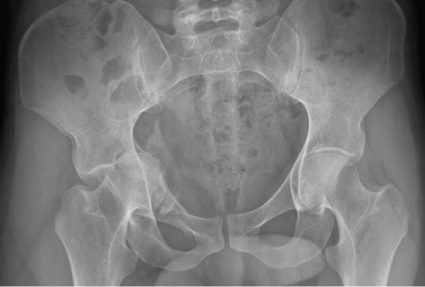

The iliopectineal fascia is subsequently detached at the level of the supero-lateral pubic ramus and Hohmann retractors are placed along the anterior column, at the level of the linea terminalis, from the anterior pubic ramus to the anterior sacroiliac joint. These retractors are aimed at protecting the external iliac vessels, the iliac psoas and the femoral nerve during the procedure. From that moment onwards, the fracture can be exposed in the mid-pelvic area (Figure 2). Lateral to the fracture, the obturator neurovascular bundle follows an oblique path, from superior-posterior to anterior-inferior, before it enters the obturator foramen. The bundle and the bladder must be protected by placing a blunt Hohmann retractor at the level of the greater sciatic notch. Placement of this retractor makes it possible to expose the posterior column up to the anterior sacroiliac joint, which will be the posterior fixation point of the osteosynthesis used. At that moment, full exposure of the fracture will have been achieved. As a technical enhancement, in cases where the dome has been impacted, the fractured quadrilateral plate can be further medialized with the help of a Cobb periosteal elevator. At the same time, lateral traction is applied to the proximal femur using a Schanz screw inserted in the lesser trochanter. This technical maneuver allows direct visualization of the impacted area. Disimpaction of the dome fracture is performed at the subchondral level, using a 10 mm scope or a Cobb periosteal elevator. Mobilization of the impacted dome creates a larger bone defect (Figure 3), which requires application of bone grafting to provide robust structural support to the dome area and prevent the dome from shifting back to the original position. We usually use cadaveric bone allograft. The fracture can now be reduced and stabilized by means of an infra-pectineal plate (Figure 4) (3.5 mm Low Profile Pelvic System, Synthes USA, Paoli, PA) supported directly on the quadrilateral plate. The fixation screws must be placed into the two posterior-most screw-holes, located in front of the anterior sacroiliac joint and into the two or three anterior screw-holes, located at iliac-publc level. In Figure 5 and Figure 6, we show a case of a patient with a transverse acetabular fracture before and after being operated by a modified Stoppa approach.

Figure 5: Transverse acetabular fracture in a 24-years-old patient before surgery. View Figure 5